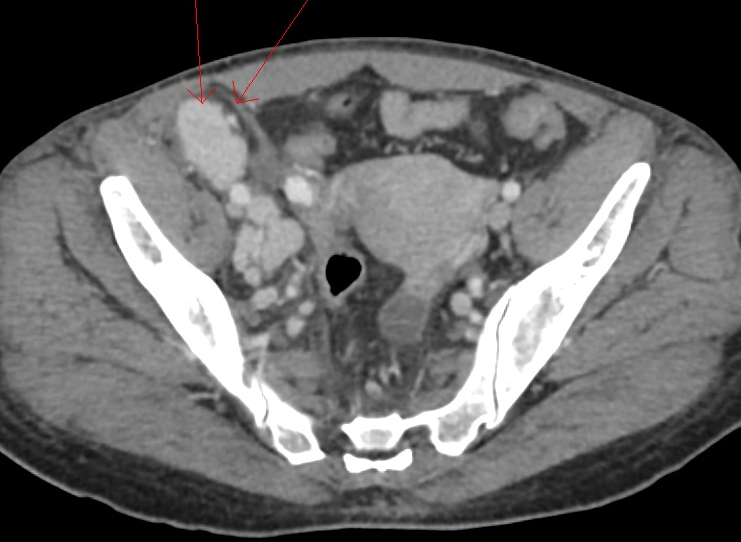

Para complementar a avaliação clínica, o ultrassom cervical é frequentemente realizado no consultório. Esse exame de imagem permite visualizar a estrutura interna do linfonodo, ajudando a diferenciar se ele tem aspecto benigno (reacional) ou suspeito. O exame é indolor, não invasivo e fornece informações valiosas para a conduta médica.

Quando os exames de imagem e o exame físico levantam suspeitas, ou quando a linfonodomegalia persiste sem causa aparente, o próximo passo pode ser a realização de uma biópsia. O procedimento mais comum é a Punção Aspirativa por Agulha Fina, conhecida como PAAF. Guiada por ultrassom, essa técnica retira algumas células do nódulo para análise laboratorial.